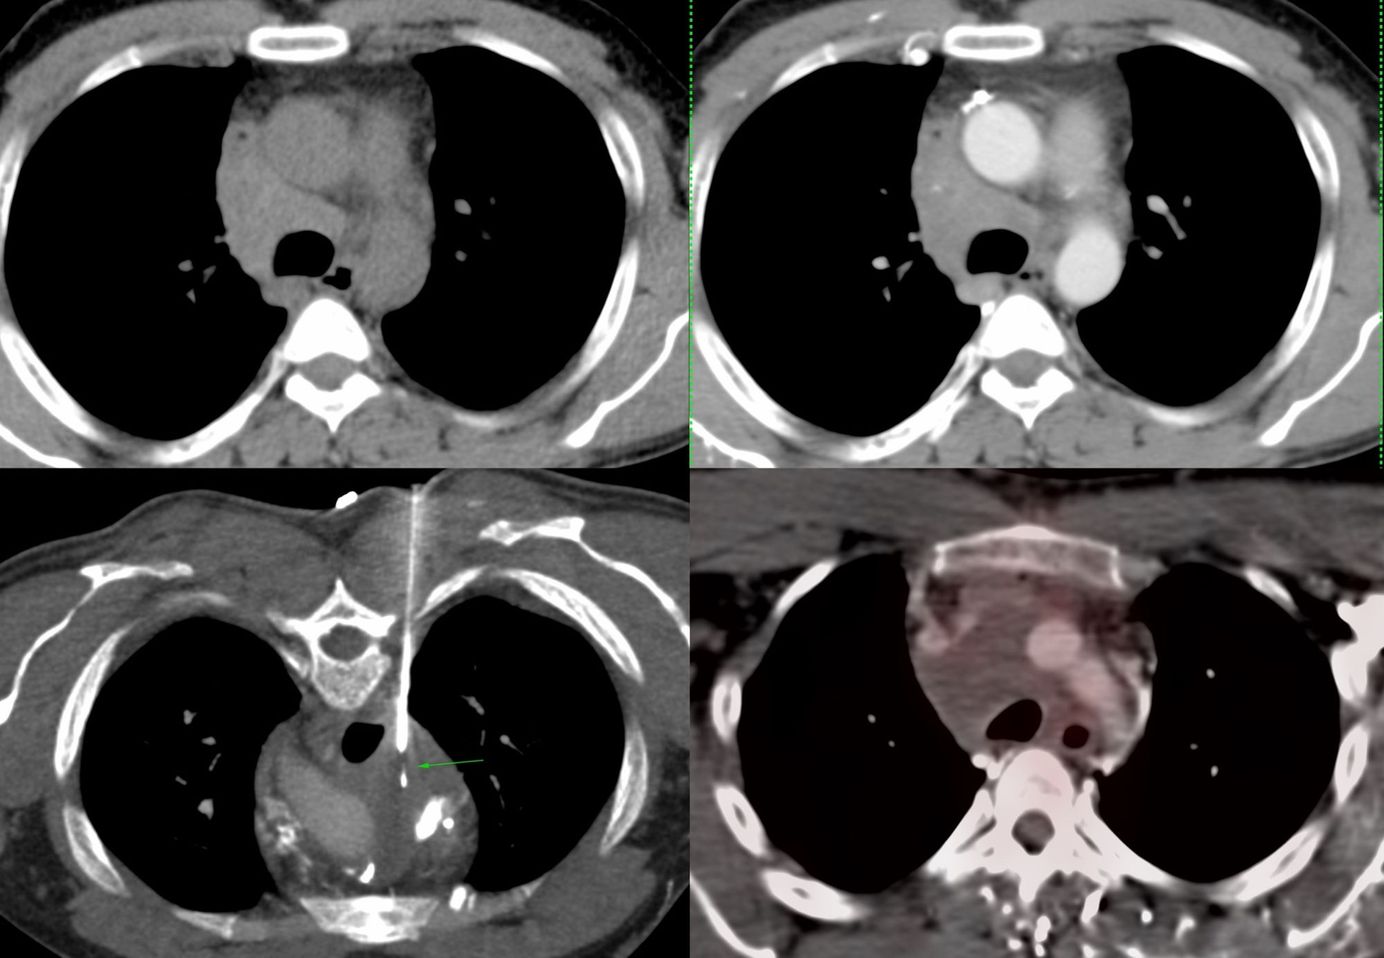

Case 14: Covid-19 Angiopathy with Perfusion Defects at 3 Weeks Members Public

3 1/2 weeks after a diagnosis of Covid-19, the lungs show extensive perfusion defects without pulmonary thrombosis